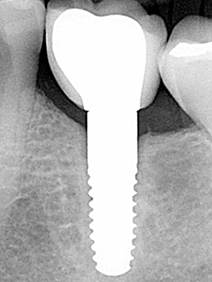

Desde los años setenta se intenta fabricar implantes dentales libres de metal con la ayuda de materiales cerámicos. Un gran avance se consigue con las máquinas de fresado guiado por ordenador CAD/CAM capaces de trabajar la extrema dureza de la cerámica dióxido de circonio.

Hasta hace poco tiempo solo existían implantes de cerámica de una sola pieza por razones técnicas. Para el implantólogo es más difícil y requiere más práctica colocar este tipo de implantes en su posición óptima. El diagnóstico en 3D es una ayuda importante para lograrlo. En los primeros 2 meses, mientras se produce la osteointegración del implante, el profesional tiene que buscar para cada caso la mejor forma para proteger el pilar del implante que sobresale de la encía contra fuerzas que puedan provocar micro movimientos del implante que harían fracasar la correcta integración, es decir, la pérdida del implante. Además, el paciente tiene que tener especial cuidado, como por ejemplo no masticar en el lado del implante insertado. Con el avance tecnológico, ya es posible contar con implantes de circonio de dos piezas parecidos a los implantes de titanio. Parece que los resultados clínicos son favorables y nos permite simplificar el protocolo.